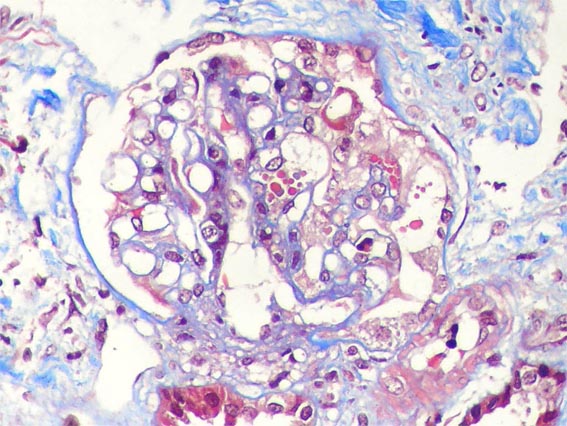

Figure 5.

Masson's

trichrome stain,

X400.